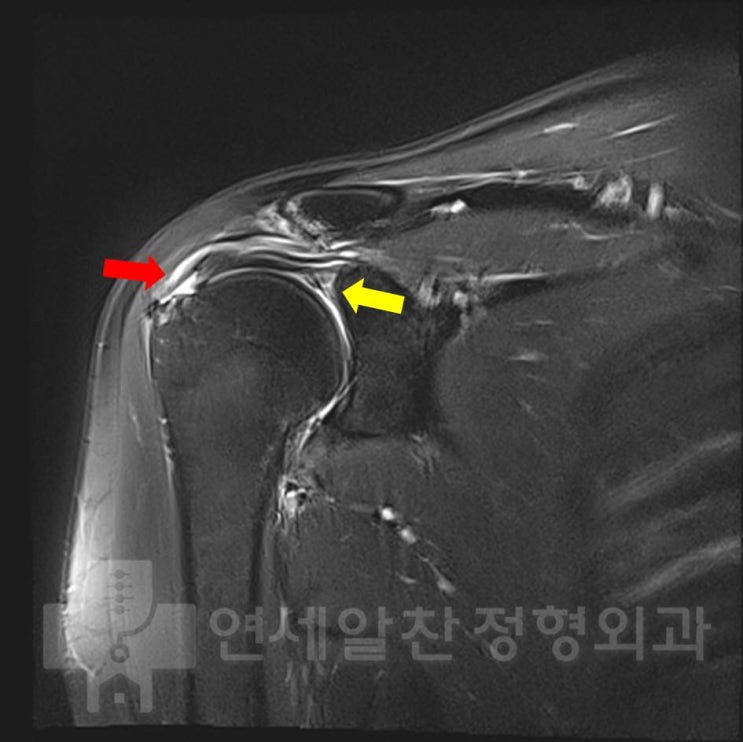

어깨 회전근개 파열에서 보강술이 필요한 경우

안녕하세요. 정형외과 전문의 이동규 입니다. 회전근개 파열이 오래 되면 혈류 제한이 있으면서 퇴행성 변...